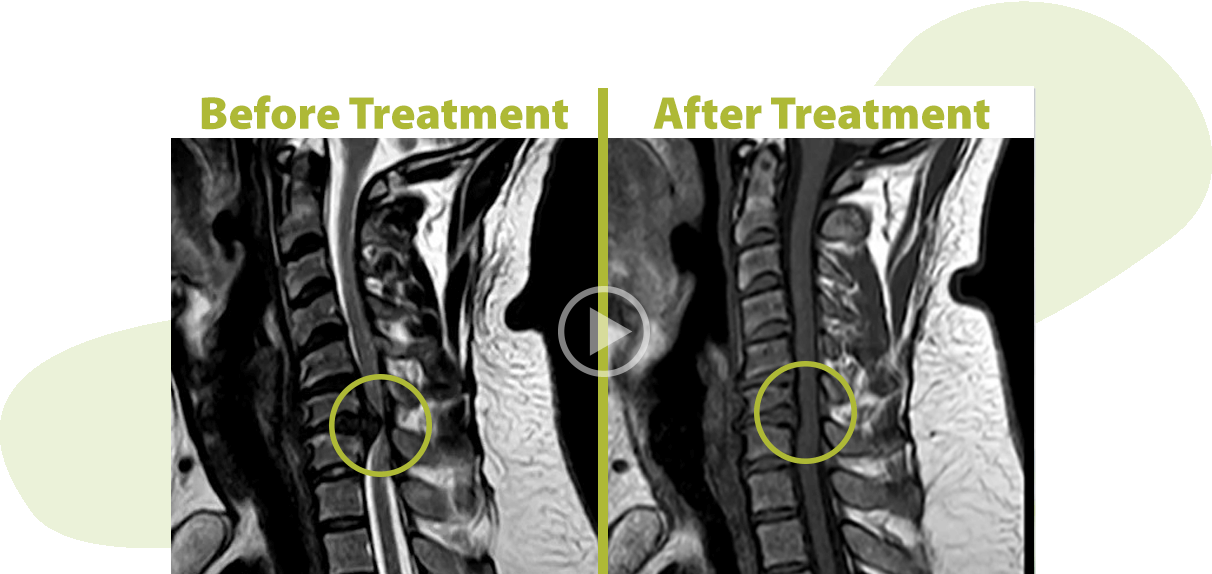

Is it possible to eliminate back pain without surgery?

Yes, back pain can be completely resolved without the use of medication, injection or surgery.

- We use USA patented technology called Spinal Decompression Treatment

See How ANSSI Spinal Decompression Technology Works for Back Pain

How Spinal Decompression Technology Works